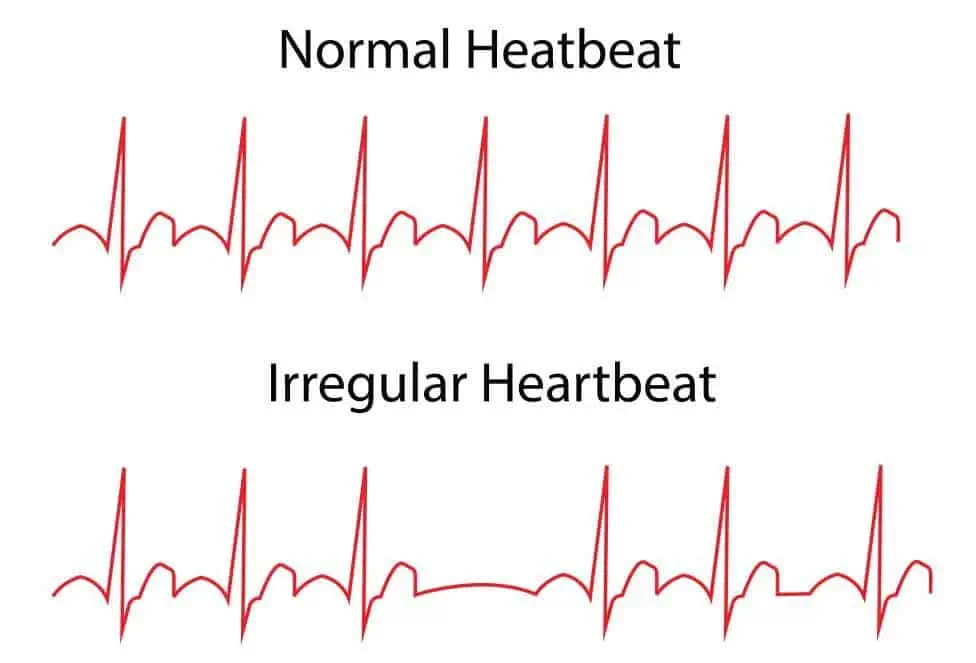

علائم بیماریهای قلبی-عروقی ناشی از ضربان غیر طبیعی (آریتمی قلب)

آریتمی قلب (heart arrhyt...